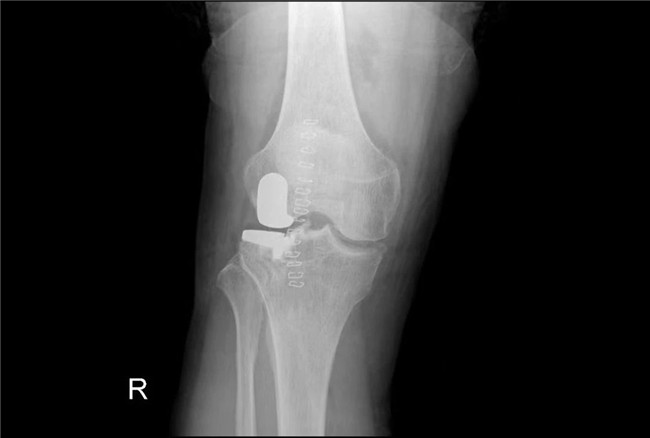

接診后羅軍主任詳細檢查病人,發(fā)現(xiàn)病人疼痛癥狀主要集中在膝關節(jié)外側(cè)間室,右下肢有明顯外翻畸形。這些癥狀都是單髁置換的適應癥。雙下肢全長攝片和右膝內(nèi)翻、外翻位攝片顯示,膝關節(jié)外側(cè)間隙消失,膝外翻畸形,果不其然印證了上述臨床表現(xiàn)。收治入院后,羅主任團隊決定為患者實施微創(chuàng)膝關節(jié)外側(cè)單髁置換術,盡全力為張大爺解除病痛的折磨。

▲術后假體位置良好,外側(cè)間隙恢復▲